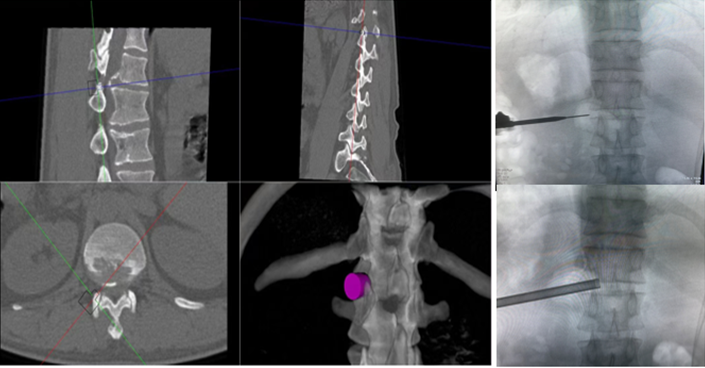

椎间孔镜在治疗脊柱相关疾病方面,尤其在治疗腰椎间盘突出症,具有创伤小、恢复快、花费少、床位周转快等优点,但椎间孔镜在术中穿刺过程中,需要反复调整穿刺针位置,需要较多的透视,特别是高位椎间盘突出症患者,稍有不慎便引起严重并发症。骨科手术机器人利用术前患者的影像学资料,模拟建立穿刺路径及各项参数,能极大地优化手术方案使其更加精准、更加安全、更加有效,显著降低了在穿刺过程中反复操作给患者造成损伤,极大程度上有效避免了严重并发症的发生。

ORTHBOT脊柱机器人术前设计及术中穿刺